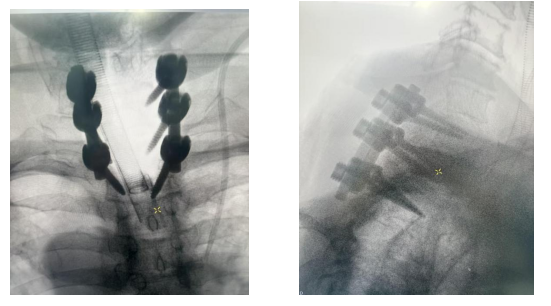

凭借机器人的亚毫米级的稳定性和三维空间精准定位能力,完美突破了传统手术的局限。术前,机器人为每一枚椎弓根螺钉的置入规划最优路径,打造精准手术「蓝图」;术中,实时导航辅助操作,全程监测、调整螺钉置入方向,从矢状位、冠状位、轴位多维度把控置钉角度,有效规避了神经、血管损伤的风险,大幅降低了手术潜在风险。同时,机器人还能实现术中即刻扫描,螺钉位置清晰可见,彻底解决了传统透视的遮挡难题。

通过与天矶机器人配合,整个手术过程顺利完成,螺钉置入位置精准无误,患者术中出血量大幅减少,手术时间也得到有效优化,手术效率和安全性实现双重提升。